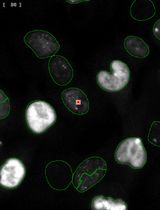

癌症生物学

利用自动化图像细胞计数法简化量化p-γ-H2AX焦点分析,以评估暴露于FLASH辐射的小鼠黑色素瘤及黑色素细胞共培养中的DNA损伤

Streamlined Quantification of p-γ-H2AX Foci for DNA Damage Analysis in Melanoma and Melanocyte Co-cultures Exposed to FLASH Irradiation Using Automated Image Cytometry

SO Stefana Orobeti

ID Ioana Dinca

AB Alexandra Bran

IT Ion Tiseanu

FS Felix Sima

SP Stefana M. Petrescu

LS Livia E. Sima

2526 Views

Feb 20, 2025

In response to DNA-damaging physical or chemical agents, the DNA damage repair (DDR) pathway is activated in eukaryotic cells. In the radiobiology field, it is important to assess the DNA damage effect of a certain irradiation regime on cancer cells and compare it to the effect on non-transformed cells exposed to identical conditions. The first step in the DNA repair mechanism consists of the attachment of proteins such as the phosphorylated histone γ-H2AX (p-γ-H2AX) to DNA double-strand breaks (DSB) in the nucleus, which leads to the formation of repairing foci. Therefore, imaging methods were established to evaluate the presence of foci inside the nucleus after exposure to DNA-damaging agents. This approach is superior in sensitivity to other methods, such as the comet assay or the pulsed-field gel electrophoresis (PFGE), that allow direct detection of cleaved DNA fragments. These electrophoresis-based methods require high ionizing radiation dosages and are difficult to reproduce compared to imaging-based assays. Conventionally, the number of foci is determined visually, with limited accuracy and throughput. Here, by exploring the effect of laser-plasma accelerated electrons FLASH irradiation on cancer cells, we describe an image cytometry protocol for the quantification of foci with increased throughput, upon large areas, with increased precision and sample-to-sample consistency. It consists of the automatic scanning of fluorescently labeled cells and using a gating strategy similar to flow cytometry to discriminate cells in co-culture based on nuclei elongation properties, followed by automatic quantification of foci number and statistical analysis. The protocol can be used to monitor the kinetics of DNA repair by quantification of p-γ-H2AX at different time points post-exposure or by quantification of other DNA repair proteins that form foci at the DNA DSB sites. Also, the protocol can be used for quantifying the response to chemical agents targeting DNA. This protocol can be performed on any type of cancer cells, and our gating strategy to discriminate cells in co-culture can also be used in other research applications.